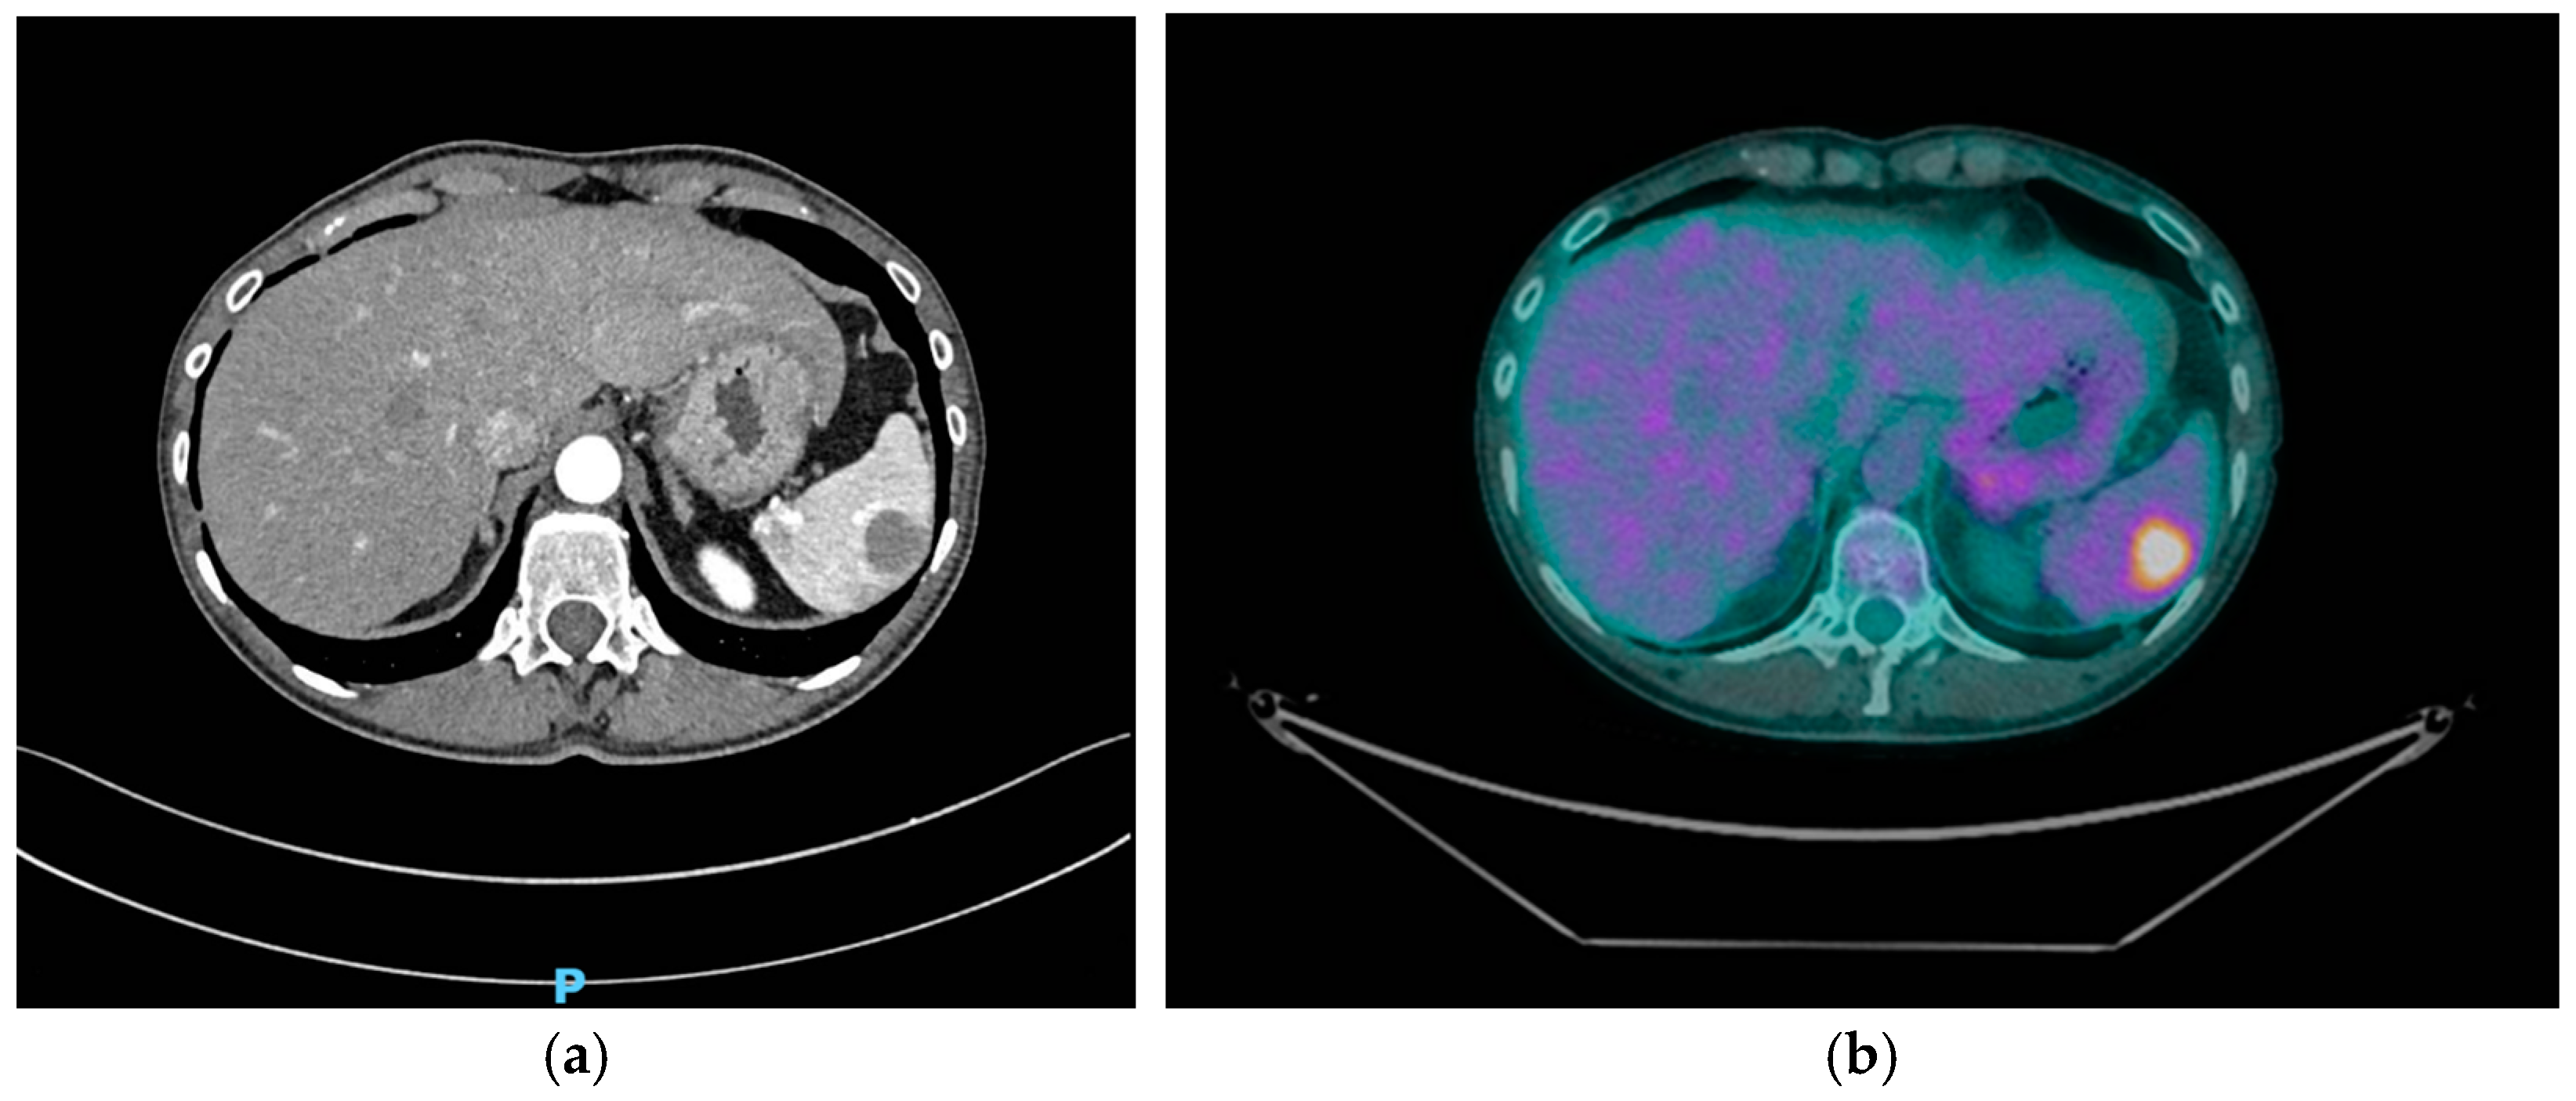

- PET-CT scan after 6 months after the last one, then every 12 months (particularly if new symptoms or imaging changes arise).